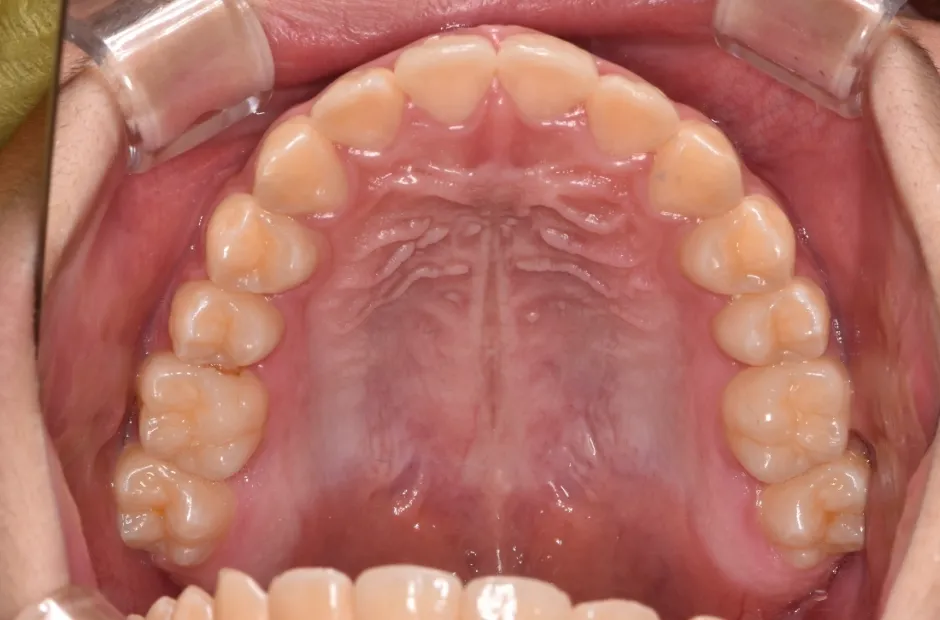

リンガルアーチ

| 診断名・主訴 | 反対咬合 |

|---|---|

| 年齢・性別 | 14歳・女性 |

| 治療期間・回数 | 2年6か月 |

| 治療に用いた主な装置 | リンガル |

| 抜歯部位 | 上顎5,5 下顎4,4 |

| 治療費 | 100万円(税抜) |

| リスク・副作用 | 装置による違和感・疼痛・歯肉退縮・歯根吸収・虫歯のリスクなど |

治療後